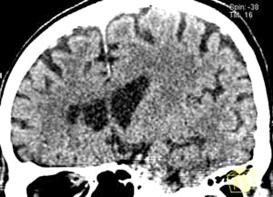

На рис.8 представлены изображения снятые при неудачном (слева) и правильном

(справа) выборе параметров съемки.

Рисунок 8

-Изображения, полученные при разных значениях параметра съемки.

Не менее важен и выбор параметров и режимов

цифровой обработки изображений.

Прежде всего, необходимо правильно выбрать

контрастность изображения (параметр контрастности называется кернелем). Влияние

величины кернеля на контрастность изображения иллюстрирует рис.9. При кернеле

40 (Рис.13а) изображение более «гладкое», при кернеле 70 (Рис.13б) изображение

более «острое». С повышением кернеля повышается контрастная разрешающая

способность. Следовательно, для визуализации мягких тканей, характеризующихся

низкой контрастностью, рекомендуется более низкийкернель (20-40). Для

визуализации высококонтрастных тканей (кости, легочная ткань) необходим более

высокий кернель (40-70), обеспечивающий высокое разрешение.

Рисунок 9

- Влияние алгоритма реконструкции на качество изображения.